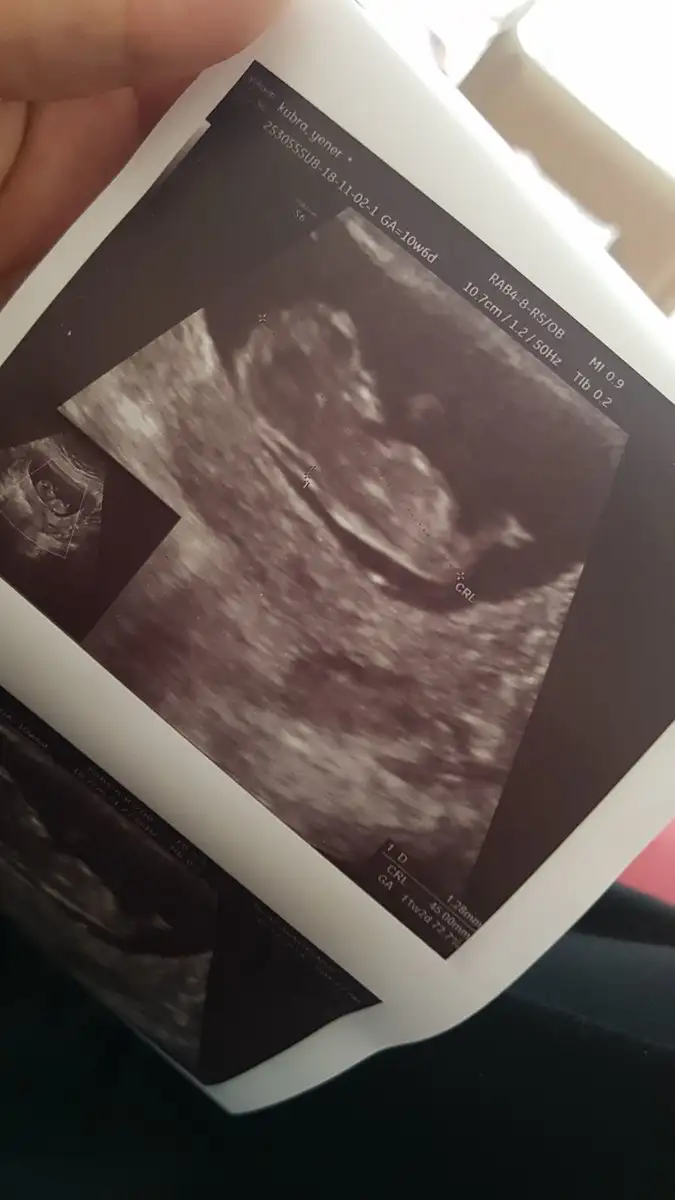

maşallah Allahım esirgesin canımMerhaba kızlar bugün doktor kontrolüm vardı 10+6 dayim üç gün geriden geliyordu sata göre şuan 11+2 cıktı üç gün de öne geçmiş maşallah yavrumu bacak arasindan cinsiyetine bakmaya çalıştık erken ama kiz gibi görünüyor dedi şuan pipi göremedik

Haftaya cuma 2 li test için gidicez resimleri atıyorum

Maşallah büyüyorlar ya :)Merhaba kızlar bugün doktor kontrolüm vardı 10+6 dayim üç gün geriden geliyordu sata göre şuan 11+2 cıktı üç gün de öne geçmiş maşallah yavrumu bacak arasindan cinsiyetine bakmaya çalıştık erken ama kiz gibi görünüyor dedi şuan pipi göremedik